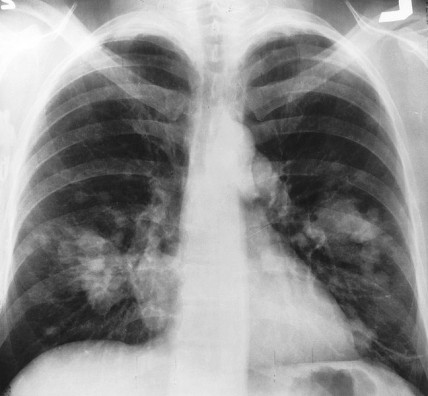

X-ray image courtesy of Wikimedia